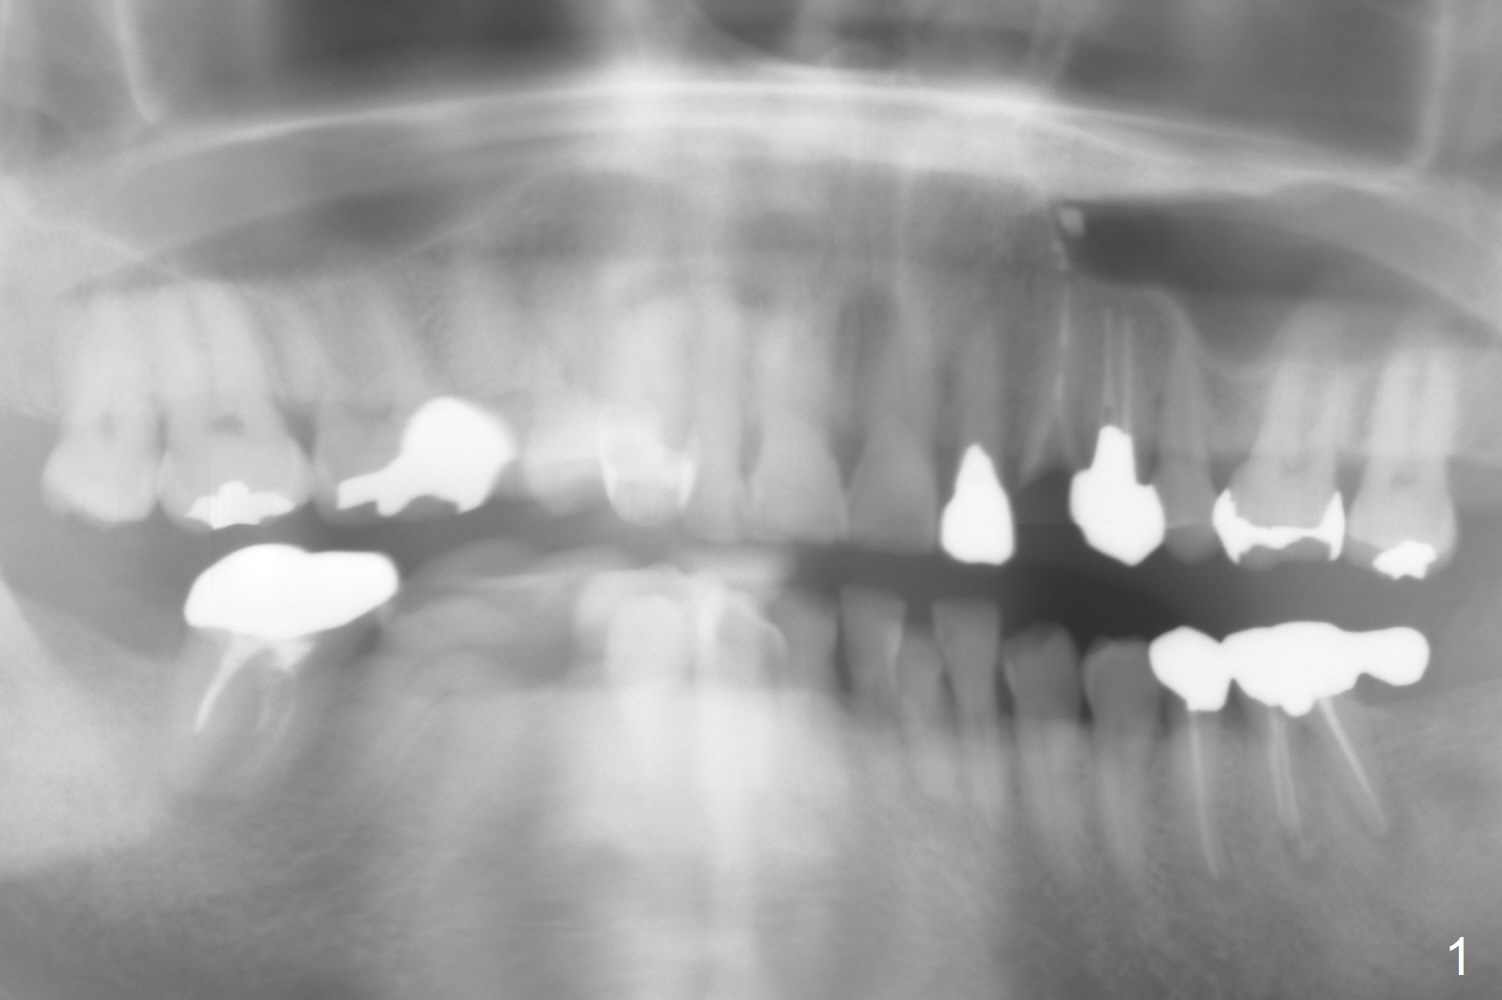

A 50-year-old man has multiple restoration (Fig.1). The tooth #11 has equigingival fracture (Fig.2). Since the labial bone is thin, socket shield will be done.